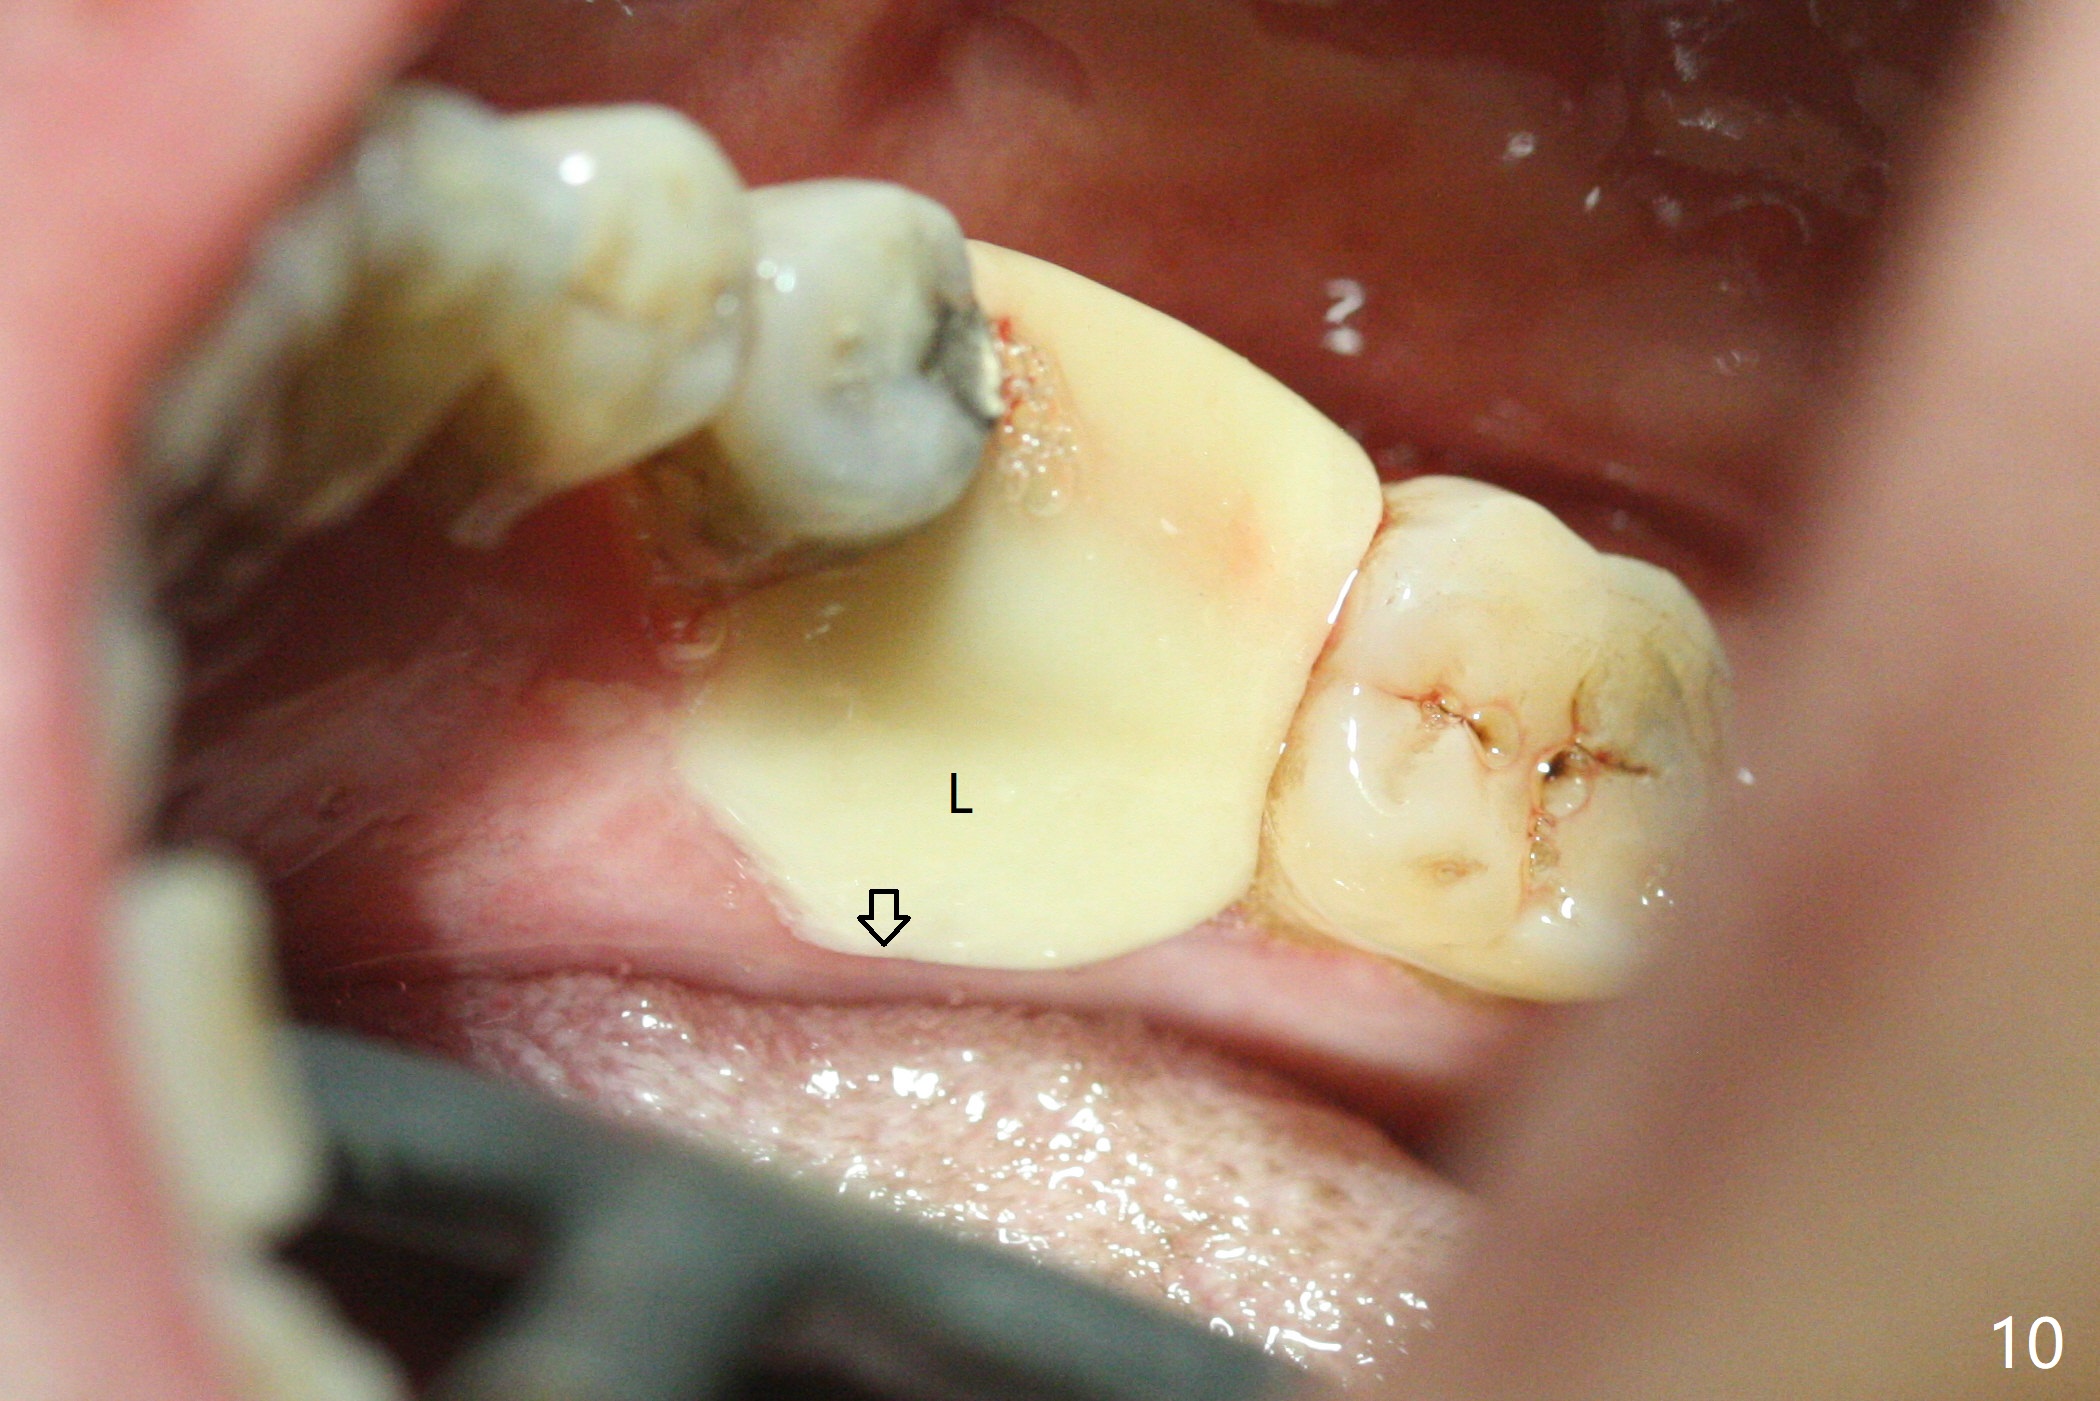

As planned, the crown of the tooth #30 with lingual (Fig.1 L) caries is removed and flattened with surgical handpiece so that the guide is able to be seated without interference. The osteotomy by 10.5 mm offset bone trimmer is lingual (Fig.2 white circle; due to in part the lingual caries and in part design error); in order to let the osteotomy to bounce back buccal, the part of the buccal roots are removed by surgical bur (arrows). The initial osteotomy by 2.2 mm drill is in the middle of the septum (Fig.3). After the last drill (3.5x11.5), the remaining roots are easily removed with proximators; a 4x11 mm dummy implant is placed with low stability and supracrestal lingual (Fig.4). Therefore a 4.5x9 mm final implant is placed with low torque. Following 4x11.5 mm drill, the torque increases to 20 Ncm. With insertion of healing screw, sticky bone (Fig.4 *: .5-1 mm cortical/cancellous allograft) is heavily packed around the implant (arrow), which apparently allows removal of the healing screw and placement of a 6x5.7(3) mm pair abutment without loosening the underlying implant. More bone graft is placed (Fig.6), followed by 2 pieces of PRF membranes. Although the implant is slightly buccally placed (Fig.7, due to over-removal of the buccal root, Fig.2 arrows), it is placed in the septum (Fig.8 S). To further compensate for the low implant stability, setting acrylic is applied in the edentulous area, particularly into the undercuts of the neighboring teeth (Fig.9 *) and around the abutment. The lingual margin of the acrylic dressing is extended (Fig.10 arrow) to cover the soft tissue defect associated with the lingual caries. As compared to the design (4x10 mm, Fig.11), the implant (4.5x9 mm, Fig.12) is placed buccal and ~ 2 mm deeper, reducing the chance of periimplantitis. The acrylic dressing is in place, but has mobility. The gingiva is healthy 2 weeks postop. The dressing is removed 1 month postop; the socket heals around the abutment buccal (Fig.13) and lingual (Fig.14). In spite of the immediate provisional, the abutment margin is substantially subgingival mesial 4 months postop, extremely difficult to take impression. A smaller diameter and longer cuff abutment is placed (Fig.15). The lingual gingiva heals normal 5 months postop, immediately before cementation (Fig.16).